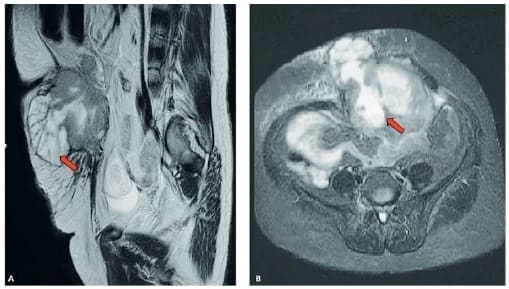

En la resonancia magnética nuclear se visualizó un tumor que involucraba el tejido celular subcutáneo y la región muscular, asociado a congestión linfática (Figura 1).

Figura 1. Pólipo pediculado de 2cm x 2cm de superficie lisa y cruenta,

localizado en la parte antero-superior del sigmoides (flecha).

Fuente: fotografía tomada por los autores.